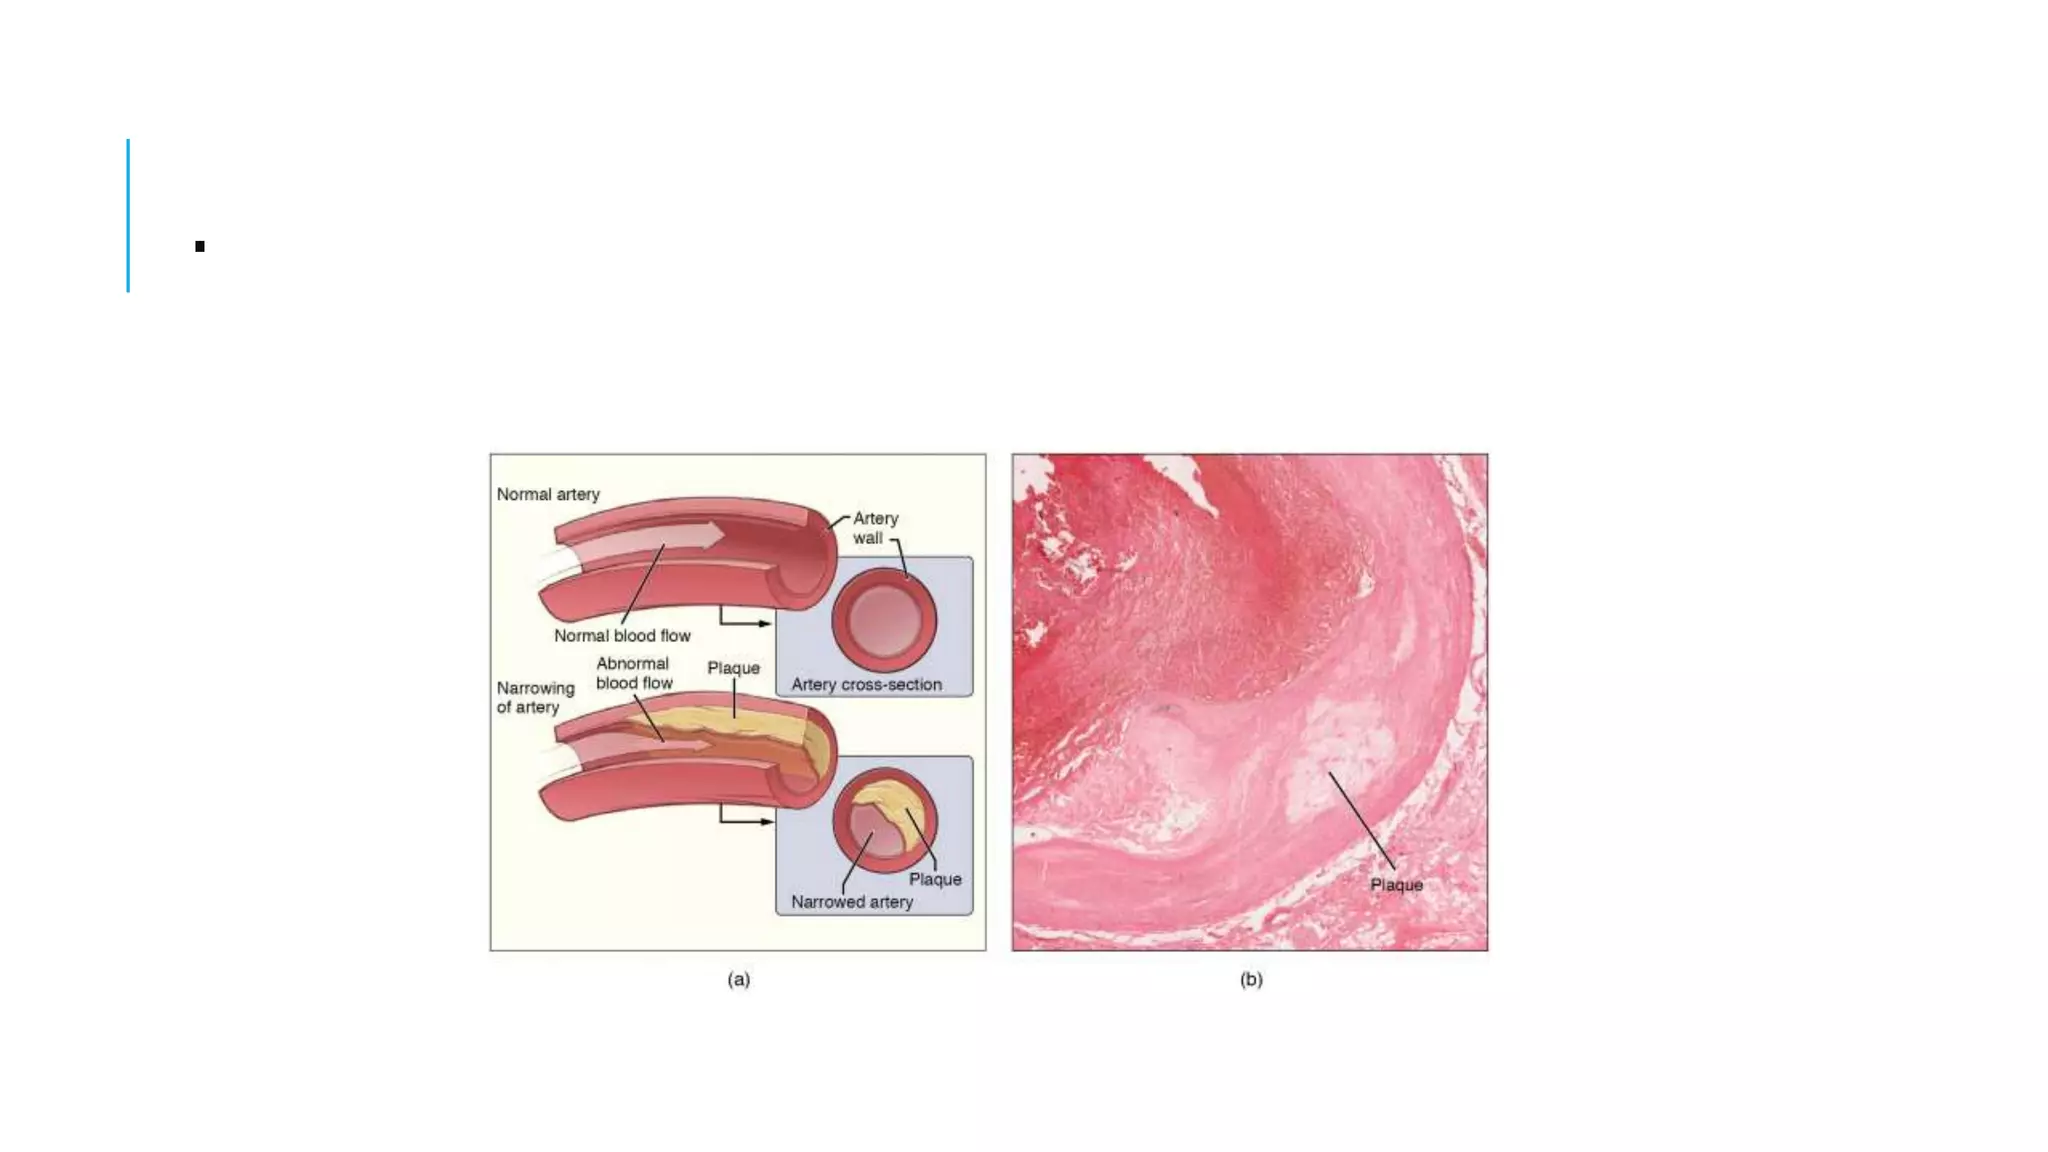

THROMBOSIS pptx

Cardiovascular Changes During Exercise